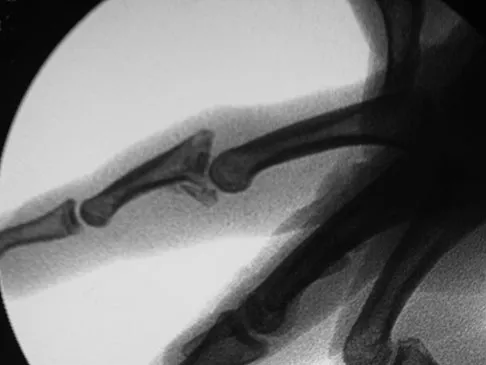

A 30-year-old woman injured the ring finger of her nondominant hand while playing baseball 5 weeks ago. She now reports pain and limited motion of the proximal interphalangeal (PIP) joint. A lateral fluoroscopy image is shown in Figure 36. Treatment of the PIP joint should consist of

Explanation